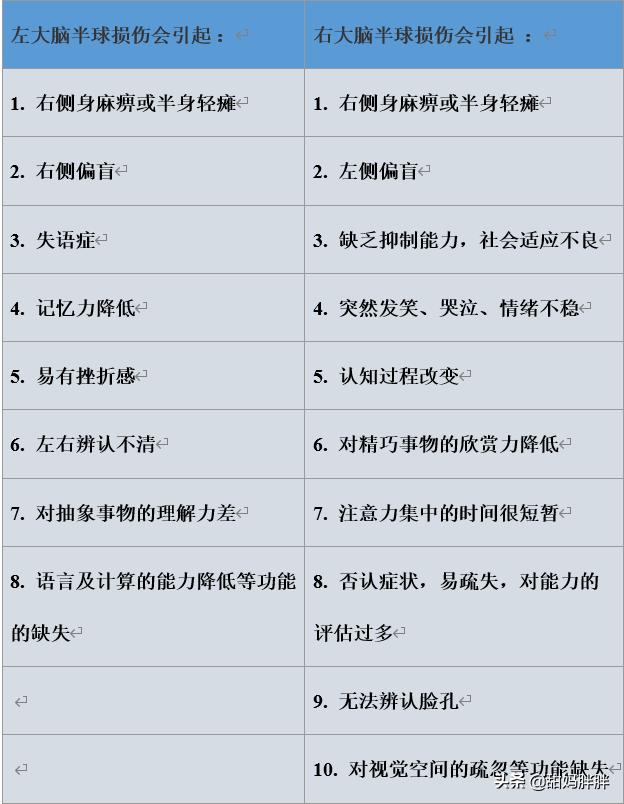

De nombreux ruraux ne reconnaissent pas l'infarctus cérébral. Qu'est-ce que l'infarctus cérébral ? L'infarctus cérébral est une maladie dans laquelle divers emboles sanguins (par exemple, un thrombus fixé à la paroi du cœur, une plaque d'athérosclérose, de la graisse, des cellules tumorales, du fibro-cartilage ou de l'air, etc.) pénètrent dans les artères cérébrales avec le flux sanguin et obstruent les vaisseaux sanguins, provoquant une nécrose ischémique des tissus cérébraux dans la zone desservie par les artères.

Pour simplifier, il s'agit de la nécrose des cellules cérébrales qui se produit lorsque les vaisseaux sanguins du cerveau sont bloqués, provoquant une ischémie cérébrale.